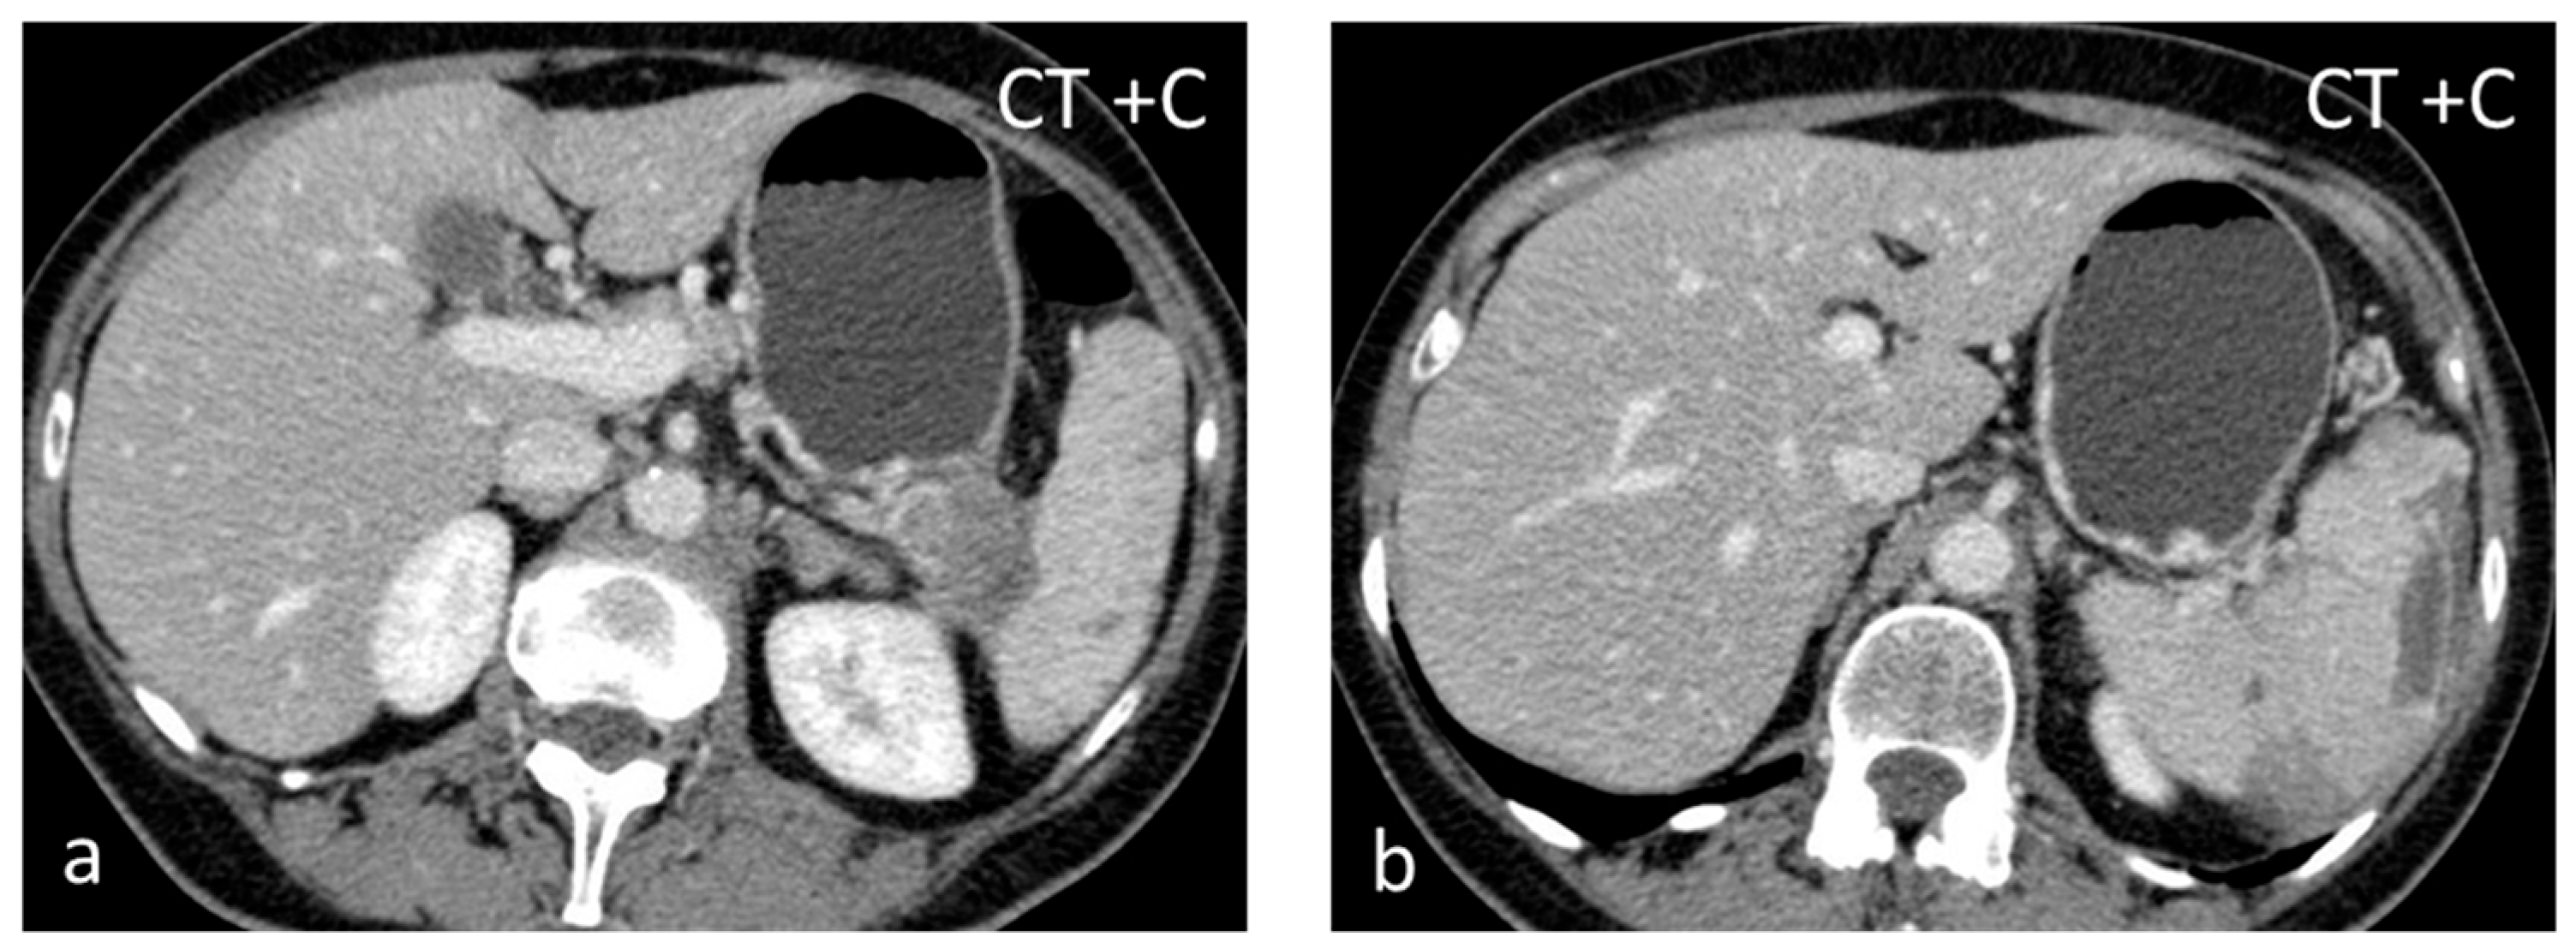

Inflammatory myofibroblastic tumor (IMT), formerly known as inflammatory pseudotumor, is an uncommon benign splenic lesion. It has been described in virtually all major organs with a few exceptions. In the liver and spleen, inflammatory pseudotumor is possibly linked to Epstein–Barr infection [13]. The prevalence is similar in both sexes, with a peak incidence in middle age. The lesions reported are usually large, measuring > 10 cm. It is composed of a combination of inflammatory and myofibroblastic spindle cells. Usually an incidental finding, it is included in the differential diagnosis of malignant splenic lesions, although currently, the World Health Organization classification of soft tissue tumors places IMTs in an intermediate category between benign and malignant, with metastases in less than 5% of extrasplenic cases [14,15]. In the US, inflammatory myofibroblastic tumors appear as solid hypoechoic masses. CT shows hypoattenuating hypoenhancing lesions, and stellate central calcifications seen on CT scans make the diagnosis very likely [16]. They present as hypointense masses both on T1-WI and T2-WI, with slow delayed enhancement (Figure 1) [17]. The diagnosis can be confirmed reliably only by histopathological and immunohistochemical evaluations. Although recurrence and metastatization have not been described for splenic inflammatory myofibroblastic tumors, patients must be followed up as these are considered tumors with intermediate malignant potential [14,17].

Figure 1.

Large solid lesion, in keeping with an inflammatory myofibroblastic tumor, slightly hypodense in the non-contrast CT scan (a), depicting slightly heterogenous/patchy gradual enhancement pattern post-contrast enhancement (b,c). The lesion appears iso– to hypointense on T2-weighted MRI, more conspicuous than in the non-contrast CT scan (d).